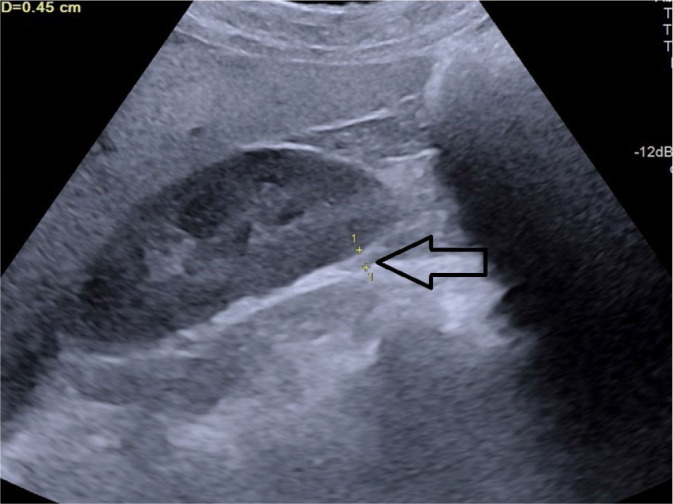

Aim: Abdominal obesity is recognized as the best predictor of cardiovascular disease risk. While body mass index has traditionally been used to measure obesity, recent evidence suggests that visceral adipose tissue may be a better indicator of cardiovascular disease risk. Various surrogate imaging markers of visceral adipose tissue have recently been described, such as posterior right perinephric fat thickness, preperitoneal fat thickness, and the abdominal wall fat index. This study aimed to examine the link between atherosclerosis through measurement of carotid intima-media thickness and markers of abdominal obesity using ultrasonography.

Material and methods: This was a hospital-based prospective observational study. Patients with a body mass index of 25-40 were included as cases and those with a body mass index 18.0-24.9 as controls. Posterior right perinephric fat thickness, preperitoneal fat thickness, and abdominal wall fat index were measured and compared with carotid intima-media thickness in cases.

Results: A total of 100 cases and 100 age- and sex-matched controls were included. Body mass index did not show any statistically significant correlations with carotid intima-media thickness in this study. Among the visceral adiposity markers, posterior right perinephric fat thickness was the most sensitive and specific predictor of carotid intima-media thickness, while the abdominal wall fat index was the least sensitive and specific.

Conclusions: Ultrasonographic markers of visceral adipose tissue, especially posterior right perinephric fat thickness and preperitoneal fat thickness, demonstrate a stronger association with carotid atherosclerosis than body mass index, making them useful predictors, particularly in individuals with high body mass index. These markers can be measured during routine abdominal ultrasounds to screen for atherosclerosis risk in patients with abdominal obesity.